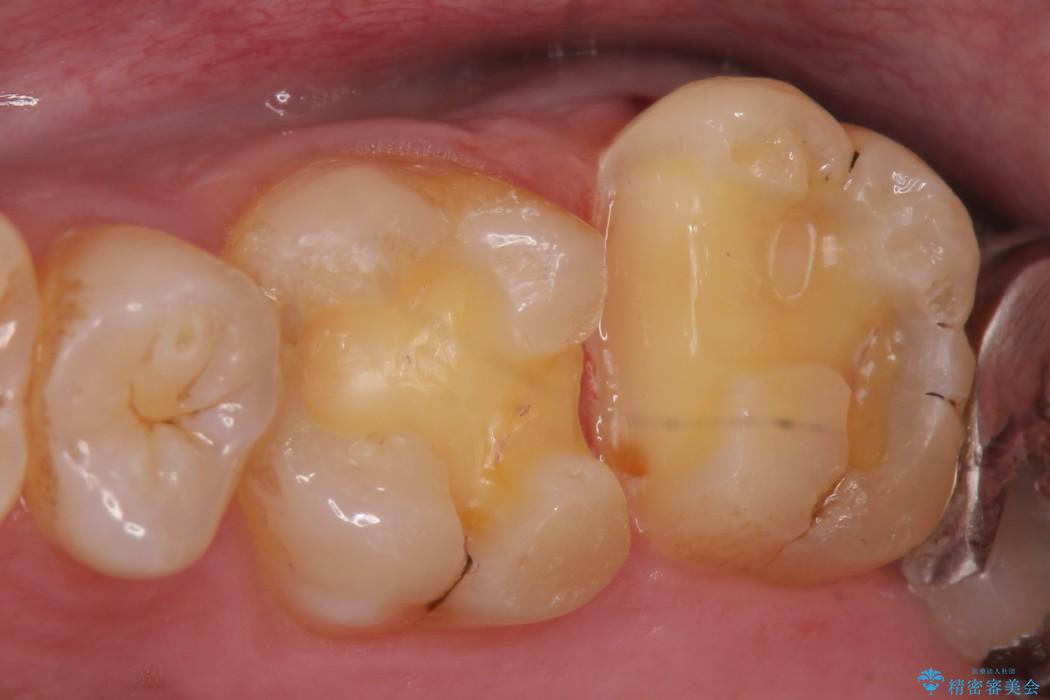

銀歯と比べて本来の歯と自然になじむ仕上がりにとてもご満足いただけました。

今回は保険で治療してあった銀歯を審美性からセラミックインレーにて再度治療しました。

セラミックスは、見た目の審美性だけでなく劣化がしにくいことや金属アレルギーのリスクがないことがメリットとしてあげられます。